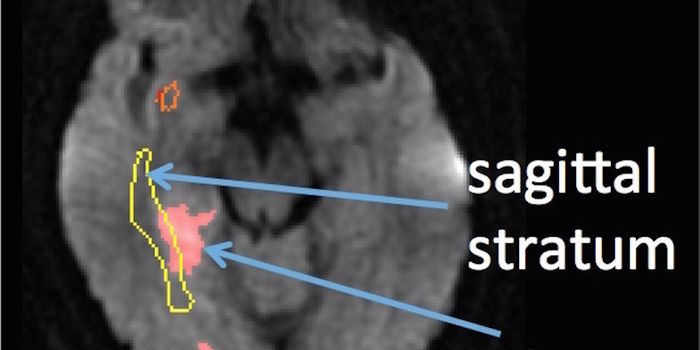

JUL 06, 2020MicrobiologyThe pandemic coronavirus has caused a wide range of different symptoms, and as time goes on, we may find that it can hav ...